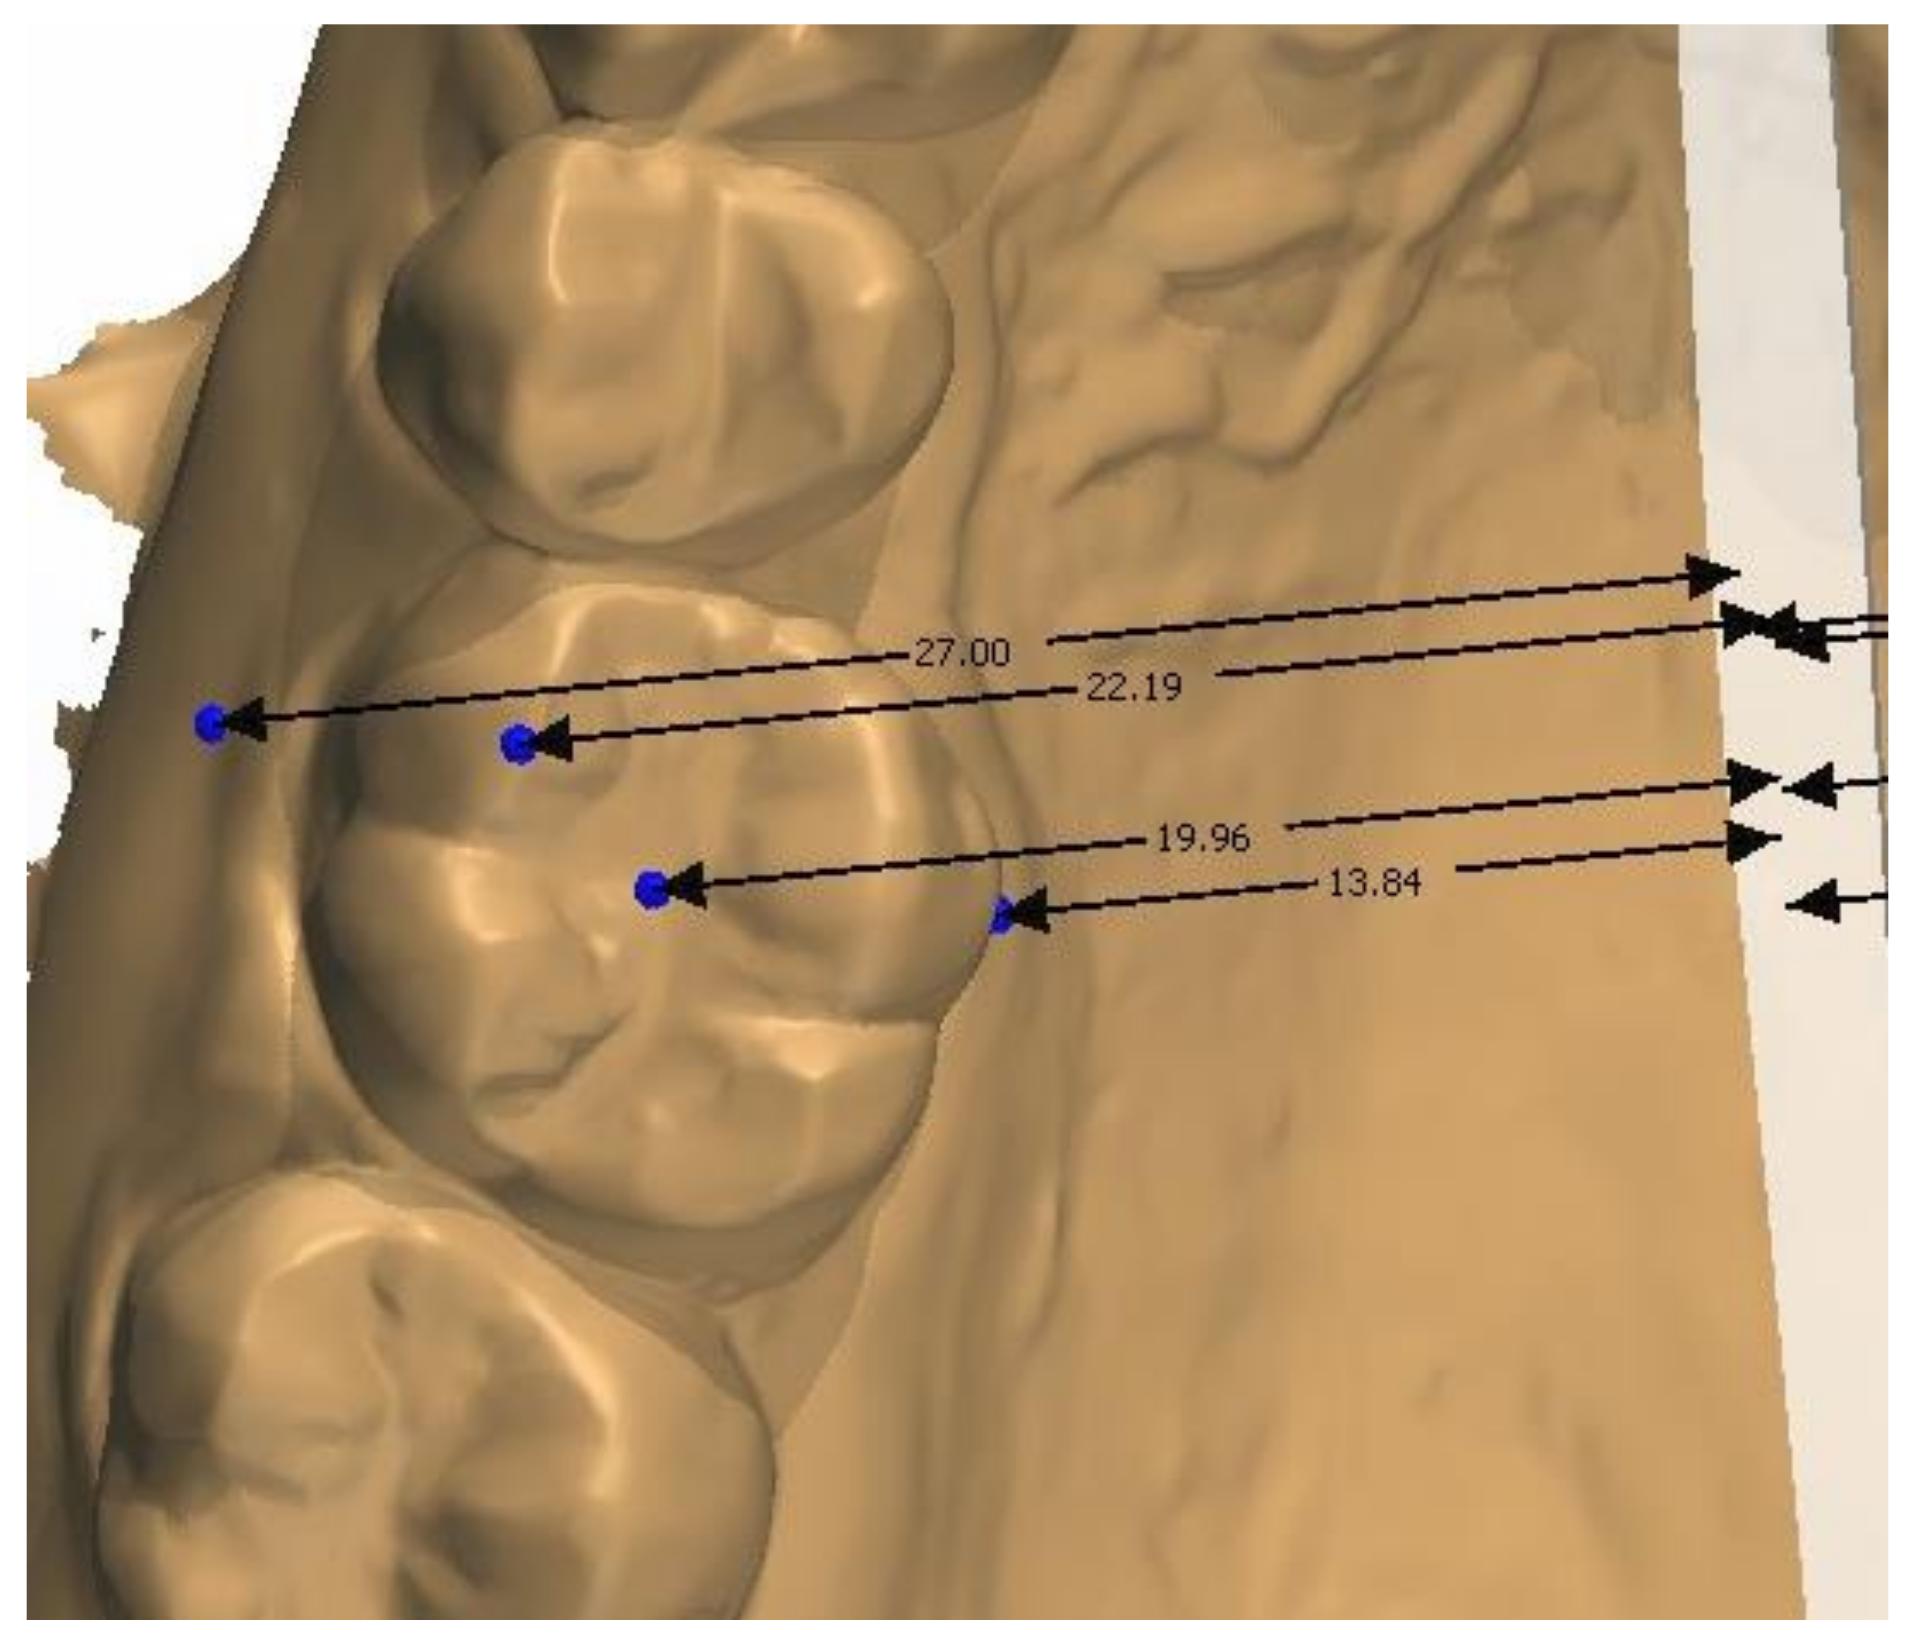

2.2. Methodology of Measurements

4.5. Transverse Measurements on CBCT Scans versus Casts